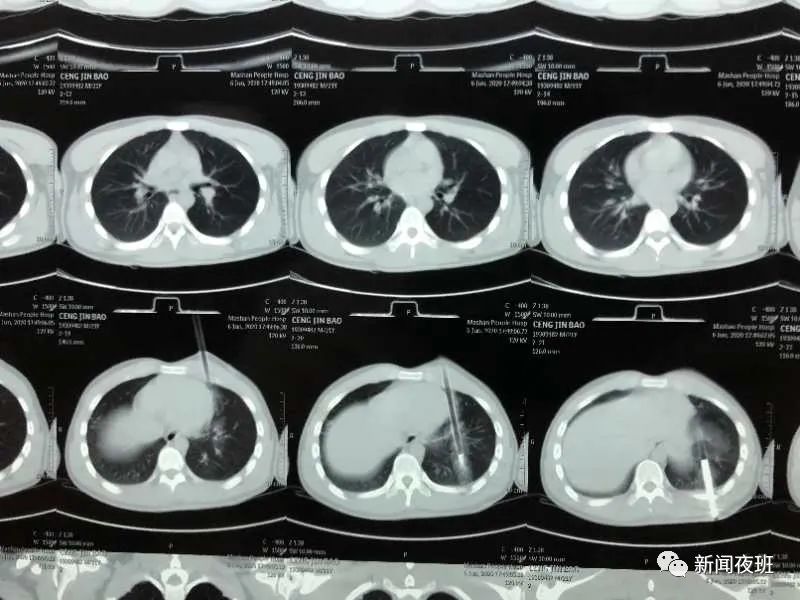

記者從廣西民族醫(yī)院了解到,這是該院胸心腺體外科的一位病人。據(jù)了解,患者是因?yàn)楸蛔约悍旁诩依锷狭颂诺腻蠹渲行目冢?月6日晚入院并進(jìn)行了急診手術(shù)。

醫(yī)生介紹,這支弩箭射穿心口距離心臟只有1cm,非常危險(xiǎn),經(jīng)過胸心腺體外科醫(yī)生手術(shù)1小時(shí)后順利取出弩箭,目前病人手術(shù)非常順利。